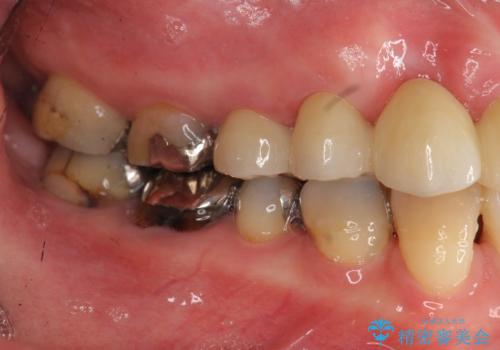

- 前歯を噛みしめにより失い、さらに犬歯もグラグラになり全く噛めなくなり改善を求めて来院されました。

過度な力がかかり周囲の骨に高度な吸収が見られた犬歯は抜歯し、機能・審美性の回復をより咬合力に対して抵抗力のあるブリッジ補綴にて対応します。